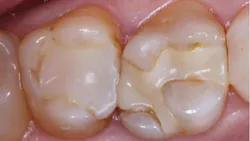

A: Your question is a common one I receive during my continuing education courses, and most dentists would agree with you. Composite restorations look good for a few years, and then caries begins again (figure 1). I shouldn’t say caries begins again. It would be better to say the organisms causing caries in the original lesion had penetrated down the dentinal tubules, and your composite restorations only put a plug in the tooth prep, leaving the organisms to continue their activity.